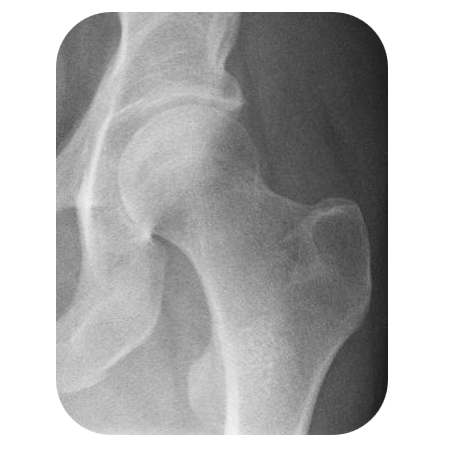

L’anca è una delle articolazioni più importanti del nostro corpo: sostiene il peso e consente ogni movimento. L’artrosi dell’anca consiste nella progressiva usura della cartilagine che riveste l’articolazione tra il femore e l’acetabolo del bacino.

L’evoluzione classica di un’artrosi dell’anca (coxartrosi) è la scomparsa progressiva della cartilagine fra l’osso della coscia (femore) e quello del bacino. Clicca QUI per saperne di più